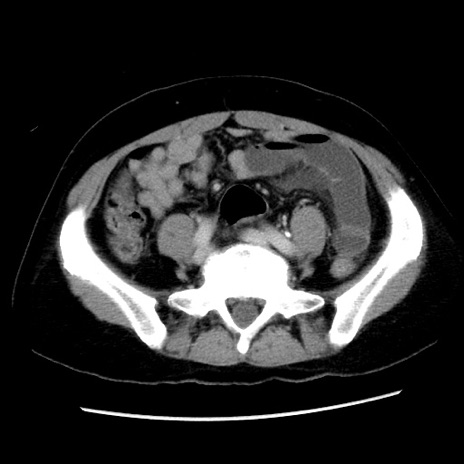

症例10(横断像)

【症例】 50歳代女性

【主訴】 腹痛

【現病歴】前日生レバーを食べた。今朝に排便あり。 昼前に突然発症の腹痛を生じ、当院救急外来を受診した。

【既往歴】 子宮筋腫にてで子宮全摘後

【身体所見】 意識清明、腹部:平坦、軟、下腹部やや左を中心に圧痛・反跳痛あり、筋性防御あり

【データ】WBC 7800、CRP 0.07